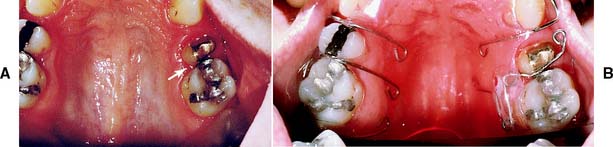

For tipping or extruding a single anterior tooth, acid-etch brackets can be used with a multistrand elastic wire ligated in place to attain the desired position. When any anterior tooth is moved, however, the amount of labial bone should be carefully evaluated and found to be adequate. Orthodontic treatment should also be considered when restorations are being used to correct a diastema. Often esthetics can be dramatically improved by distributing the space of a midline diastema around all the anterior teeth (Fig. 6-25A to C). A diagnostic waxing procedure will help determine the optimum tooth position. Uprighting a mesially tilted molar can be accomplished with a coil spring (see Fig. 6-25D to G), but the tooth should first be adjusted out of occlusion. A neglected crown preparation can be salvaged with a simple orthodontic appliance (Fig. 6-26). All orthodontic movement requires adequate anchorage so that inadvertent movement of other teeth is avoided.

Fig. 6-26 A, The maxillary premolar (arrow) was prepared for a metal-ceramic crown but was inadequately provisionalized. Unfortunately, the patient failed to return when the interim restoration became dislodged. The tooth had moved distally and was in contact with the first molar, making crown placement impossible. B, A removable appliance was used to reposition the tooth before impression making.